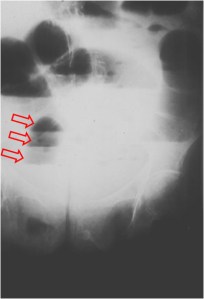

SIGNO DE LA ESCALERA

Signo visto en la radiografía simple de abdomen en la obstrucción intestinal, llamado así por el aspecto de las asas intestinales dilatadas y rellenas de aire, superpuestas unas sobre otras (flechas).